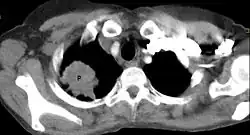

Guz Pancoasta (zespół Pancoasta, ang. Pancoast syndrome) – szczególna postać kliniczna raka oskrzela, zlokalizowanego obwodowo w okolicy szczytu płuca mogący naciekać żebra, kręgi, ścianę klatki piersiowej i struktury otworu górnego klatki piersiowej. Guz Pancoasta musi naciekać opłucną ścienną i wywoływać objawy neurologiczne, sama lokalizacja w szczycie płuca nie wystarcza do klasyfikacji nowotworu płuc jako guza Pancoasta[1]. Często dochodzi do uszkodzenia splotu ramiennego i zwoju gwiaździstego[1]. Stanowi około 5% przypadków raka płuc[2].

Około 70% guzów stanowi gruczolakorak, resztę stanowi rak drobnokomórkowy i olbrzymiokomórkowy[2]. Pierwszym objawem bywa stały ból okolicy barku, łopatki, a czasami także ramienia spowodowany uciskiem lub naciekaniem splotu ramiennego, opłucnej ściennej, żeber I-III; jest to ból charakterystyczny dla tej choroby[3]. Charakterystyczny jest zespół objawów neurologicznych spowodowanych uciskiem splotu barkowego oraz zespół Hornera (m.in. ptoza, mioza, enoftalmia) spowodowany uciskiem lub naciekaniem zwojów współczulnych. Guz Pancoasta z definicji jest zaawansowanym nowotworem (guzy T3 i T4 w klasyfikacji TNM)[2].